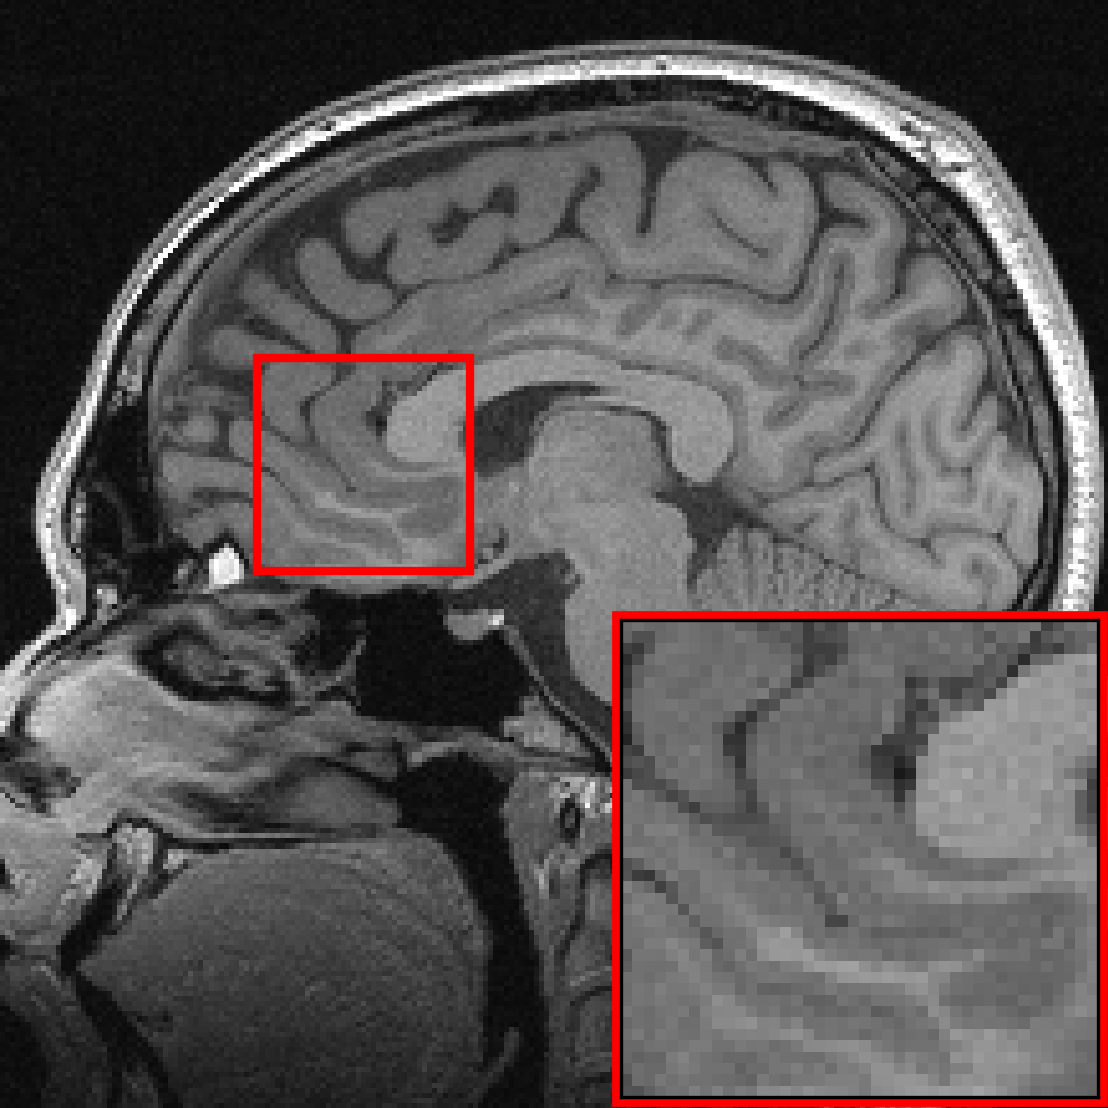

Many of our experiments are based on splits of the fastMRI dataset [Zbo+19], the most commonly used dataset for MRI reconstruction research. Figure 1 depicts samples from the fastMRI dataset and shows that MRI data varies significantly in appearance across different anatomies and image contrasts (FLAIR, T1, PD, etc). The image distribution also varies across vendors and magnetic field strengths of scanners, as the strength of the magnet impacts the signal-to-noise ratio (SNR), with stronger magnets leading to higher SNRs.

We see that the models trained on show essentially the same performance (SSIM) as models trained on regardless of pathology size. The results indicate that models trained on images without pathologies can reconstruct pathologies as accurately as models trained on images with pathologies. This is further illustrated in Figure 6 (and Figure 16), where we show reconstructions given by the VarNet of images with a pathology: the model recovers the pathology well even though no pathologies are in the training set. Figure 14 in the appendix provides a more nuanced evaluation of the SSIM values for VarNet.